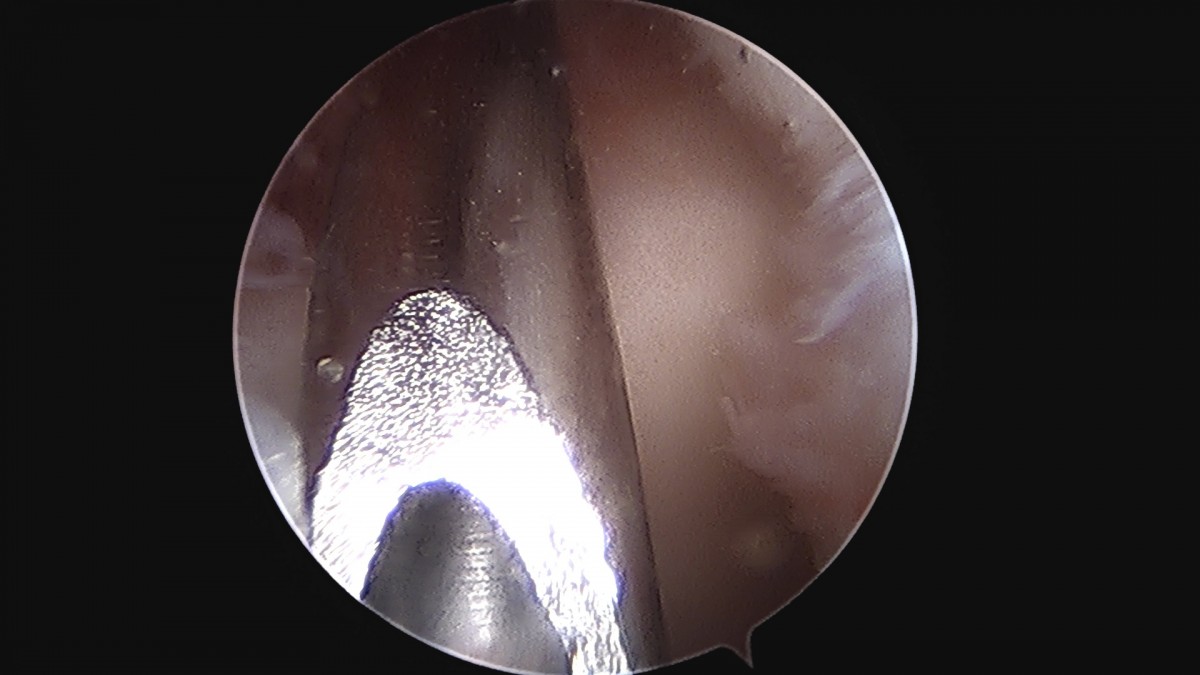

정지영원장님 손목 삼각섬유연골 복합체 봉합술 박현O 환자

dae765e4d9ac96aee867c9d6292d8784_1758009003_6955.jpg